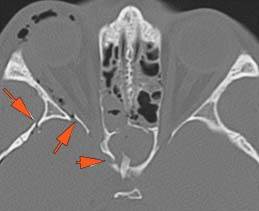

Mandible and Temporomandibular Joints

There is bony injury or displacement of the any part of the of the mandible including the condylar head and fossa.